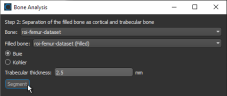

Options for automatically segmenting cortical and trabecular areas, as well as for computing global measurements (see Computing Global Measurements), are available in the Bone Analysis dialog, shown below. Results can be output in comma-separated values files (*.csv extension).

Bone Analysis dialog

- Make sure that you are on the Separation of the filled bone as cortical and trabecular bone screen of the Bone Analysis dialog.

- Select the region of interests that will provide the inputs for segmenting cortical and trabecular bone in the Bone and Filled bone drop-down menus.

You can select the filled region of interest you created in the previous step, an edited region of interest, or any other region of interest that satisfies the required criteria.

- Choose a segmentation method — Kohler or Buie — to segment cortical and trabecular bone.

- Enter the expected maximal thickness of the trabeculae in the Trabecular thickness edit box.

- Click the Segment button to start the automated segmentation routine.